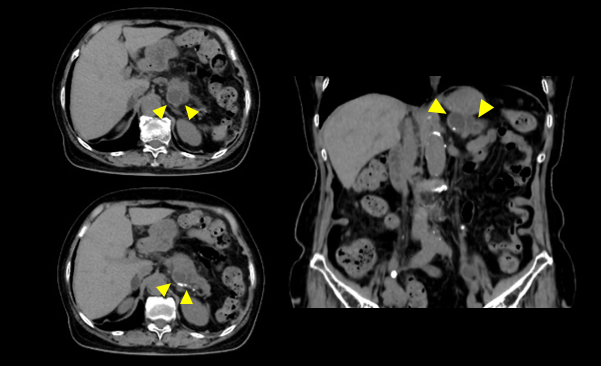

当院では造影検査も行なっており平衡相造影によるメタ検査はもちろん、HCC疑いでは栄養血管特定の動脈相(CT Angio撮影含む)、門脈相、静脈相画像も収集しています。 [画像②]

actcv_sakamoto_naika_03_big.png

[画像②] HCC